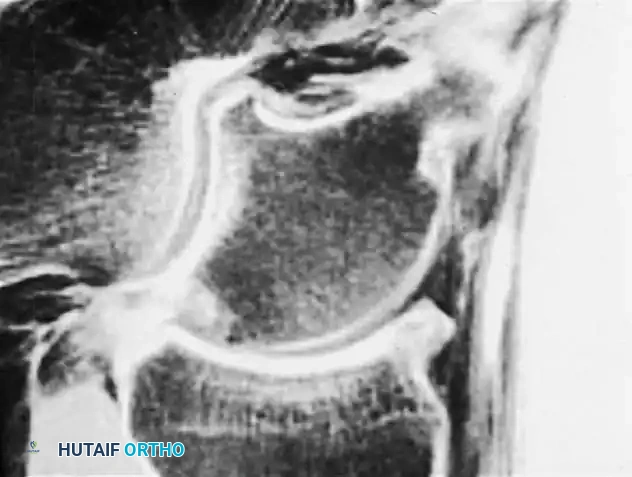

Fig. 4: Diagnostic imaging of an avulsion fracture of the talus. Left: Bone scan demonstrating focal uptake. Right: CT scan confirming the exact morphology of the posterolateral process fracture.

Avulsion Fractures of the Talus

Fractures of the lateral processes of the talus (inferolateral or posterolateral) are often termed "snowboarder's fractures." They occur during forced dorsiflexion and inversion. Standard radiographs frequently miss these lesions due to osseous overlap.